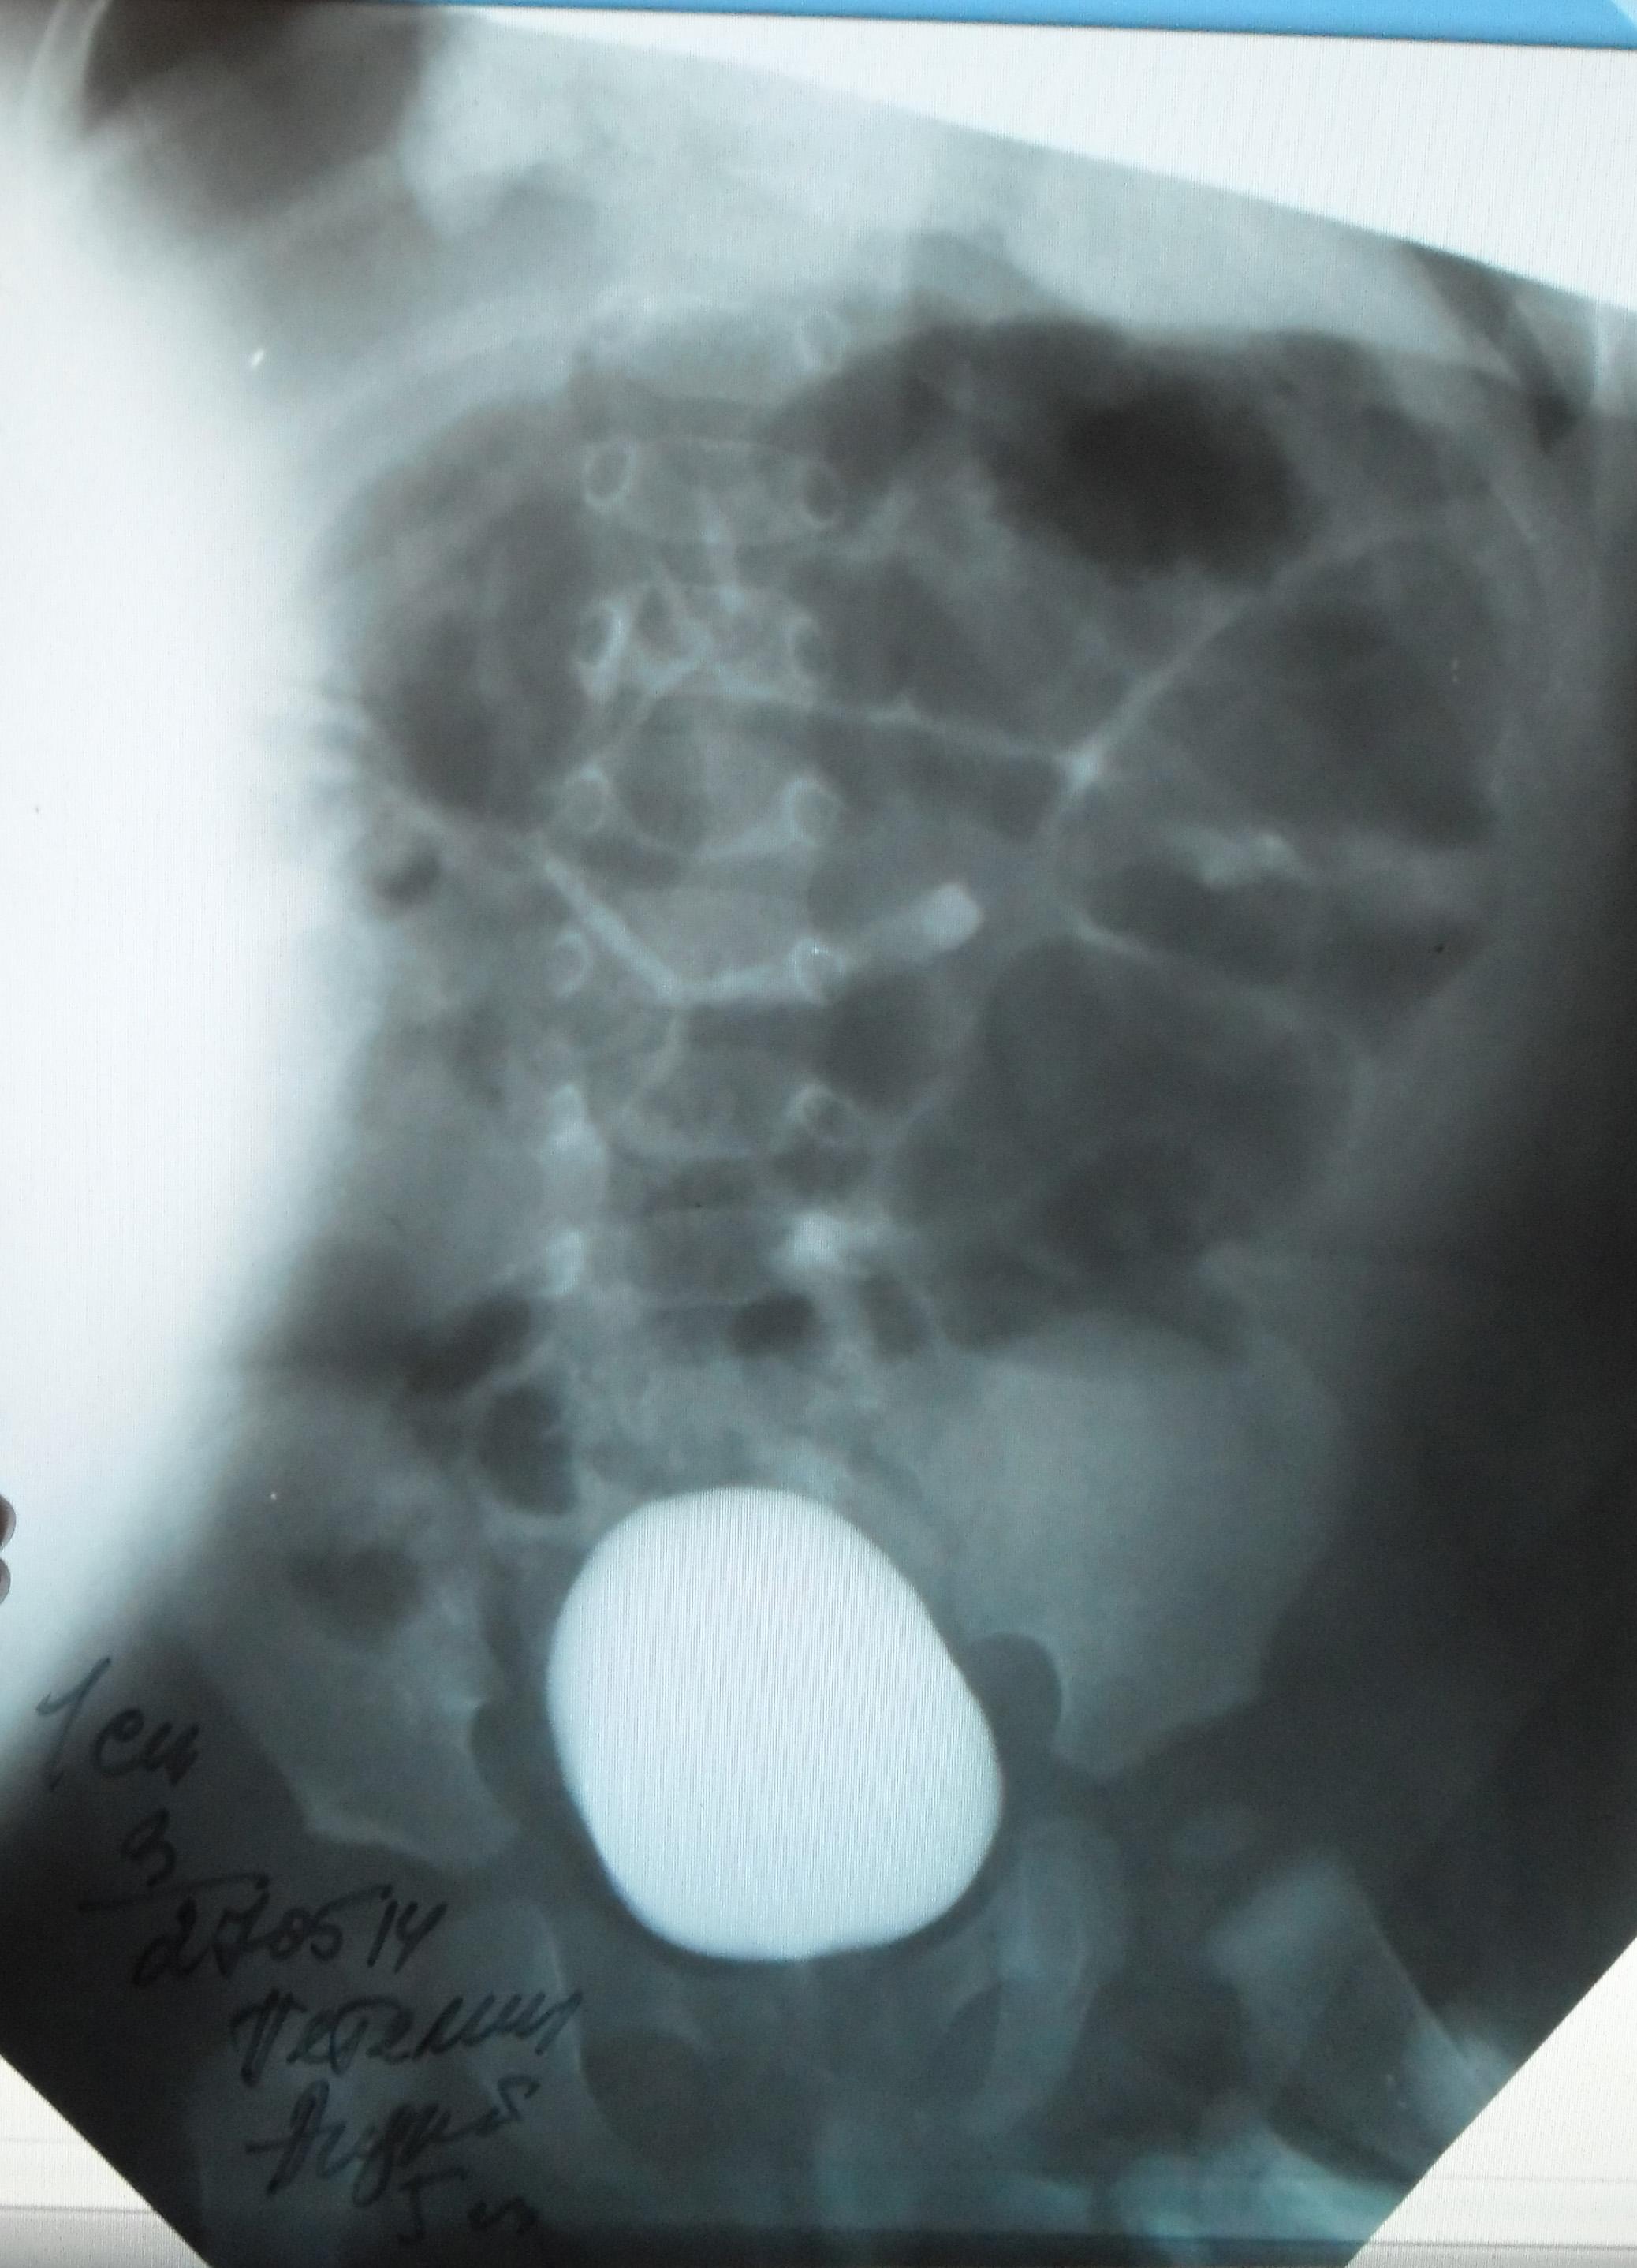

Моему ребенку 1 год 1 месяц. Во время беременности у плода было обнаружено увеличение лоханки слева - 9мм. Далее по результатам УЗИ после рождения максимальное увеличение достигало 17 мм. В 5 месяцев проходили урологическое обследование, результаты цистографии: мочевой пузырь округлой формы. Контуры ровные. ПМР нет. ЭЭД-1,2МЗВ; урографии: рентгеноконтрастных теней конкремента нет, почки в типичном месте, размеры сохранены, структура ЧЛК справа не изменена, слева пиелоэктазия, подвижность допустима, функция сохранена, ЭЭД – 0,4 МЗВ. По последнему УЗИ (1 год) увеличение лоханки слева - 28 мм. Мочеточники и сама почка в норме. Результаты анализов мочи за этот год хорошие (сдавали ежемесячно). В чем могут быть причины данного явления и чем это грозит малышу?

Ответ врача

В данном случае - сужение лоханочно-мочеточникового сегмента и\или добавочный сосуд(слева). Но выделительная функция почки сохранена. В данный момент целесообразно наблюдение, но в дальнейшем - не исключено хирургическое вмешательство.